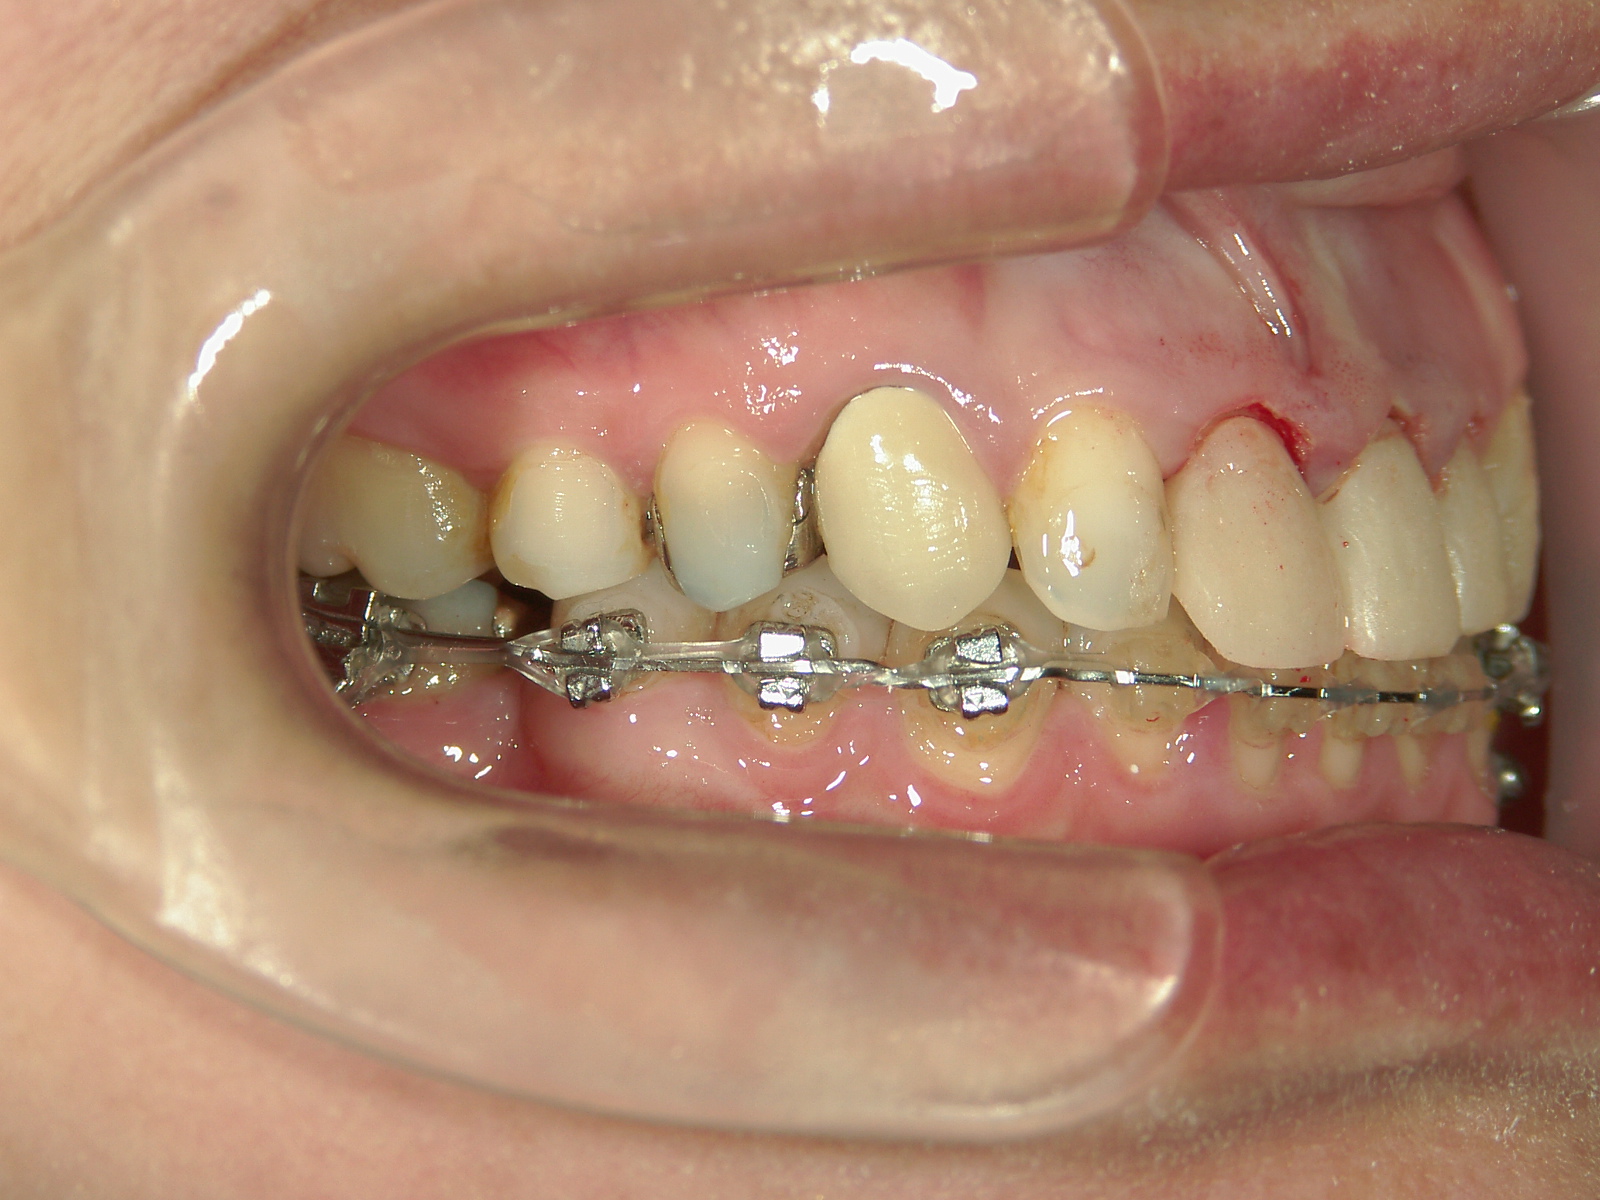

抜歯欠損症例(7)右下大臼歯 欠損・左下大臼歯 抜歯

主訴: 前歯揃えて引っ込めたい

右下 第一大臼歯 欠損。

右上 親不知1本、左下 第一大臼歯1本を抜歯。

ミニインプラント併用。

㊤前歯2本冠せ物をセラミックへ変更。